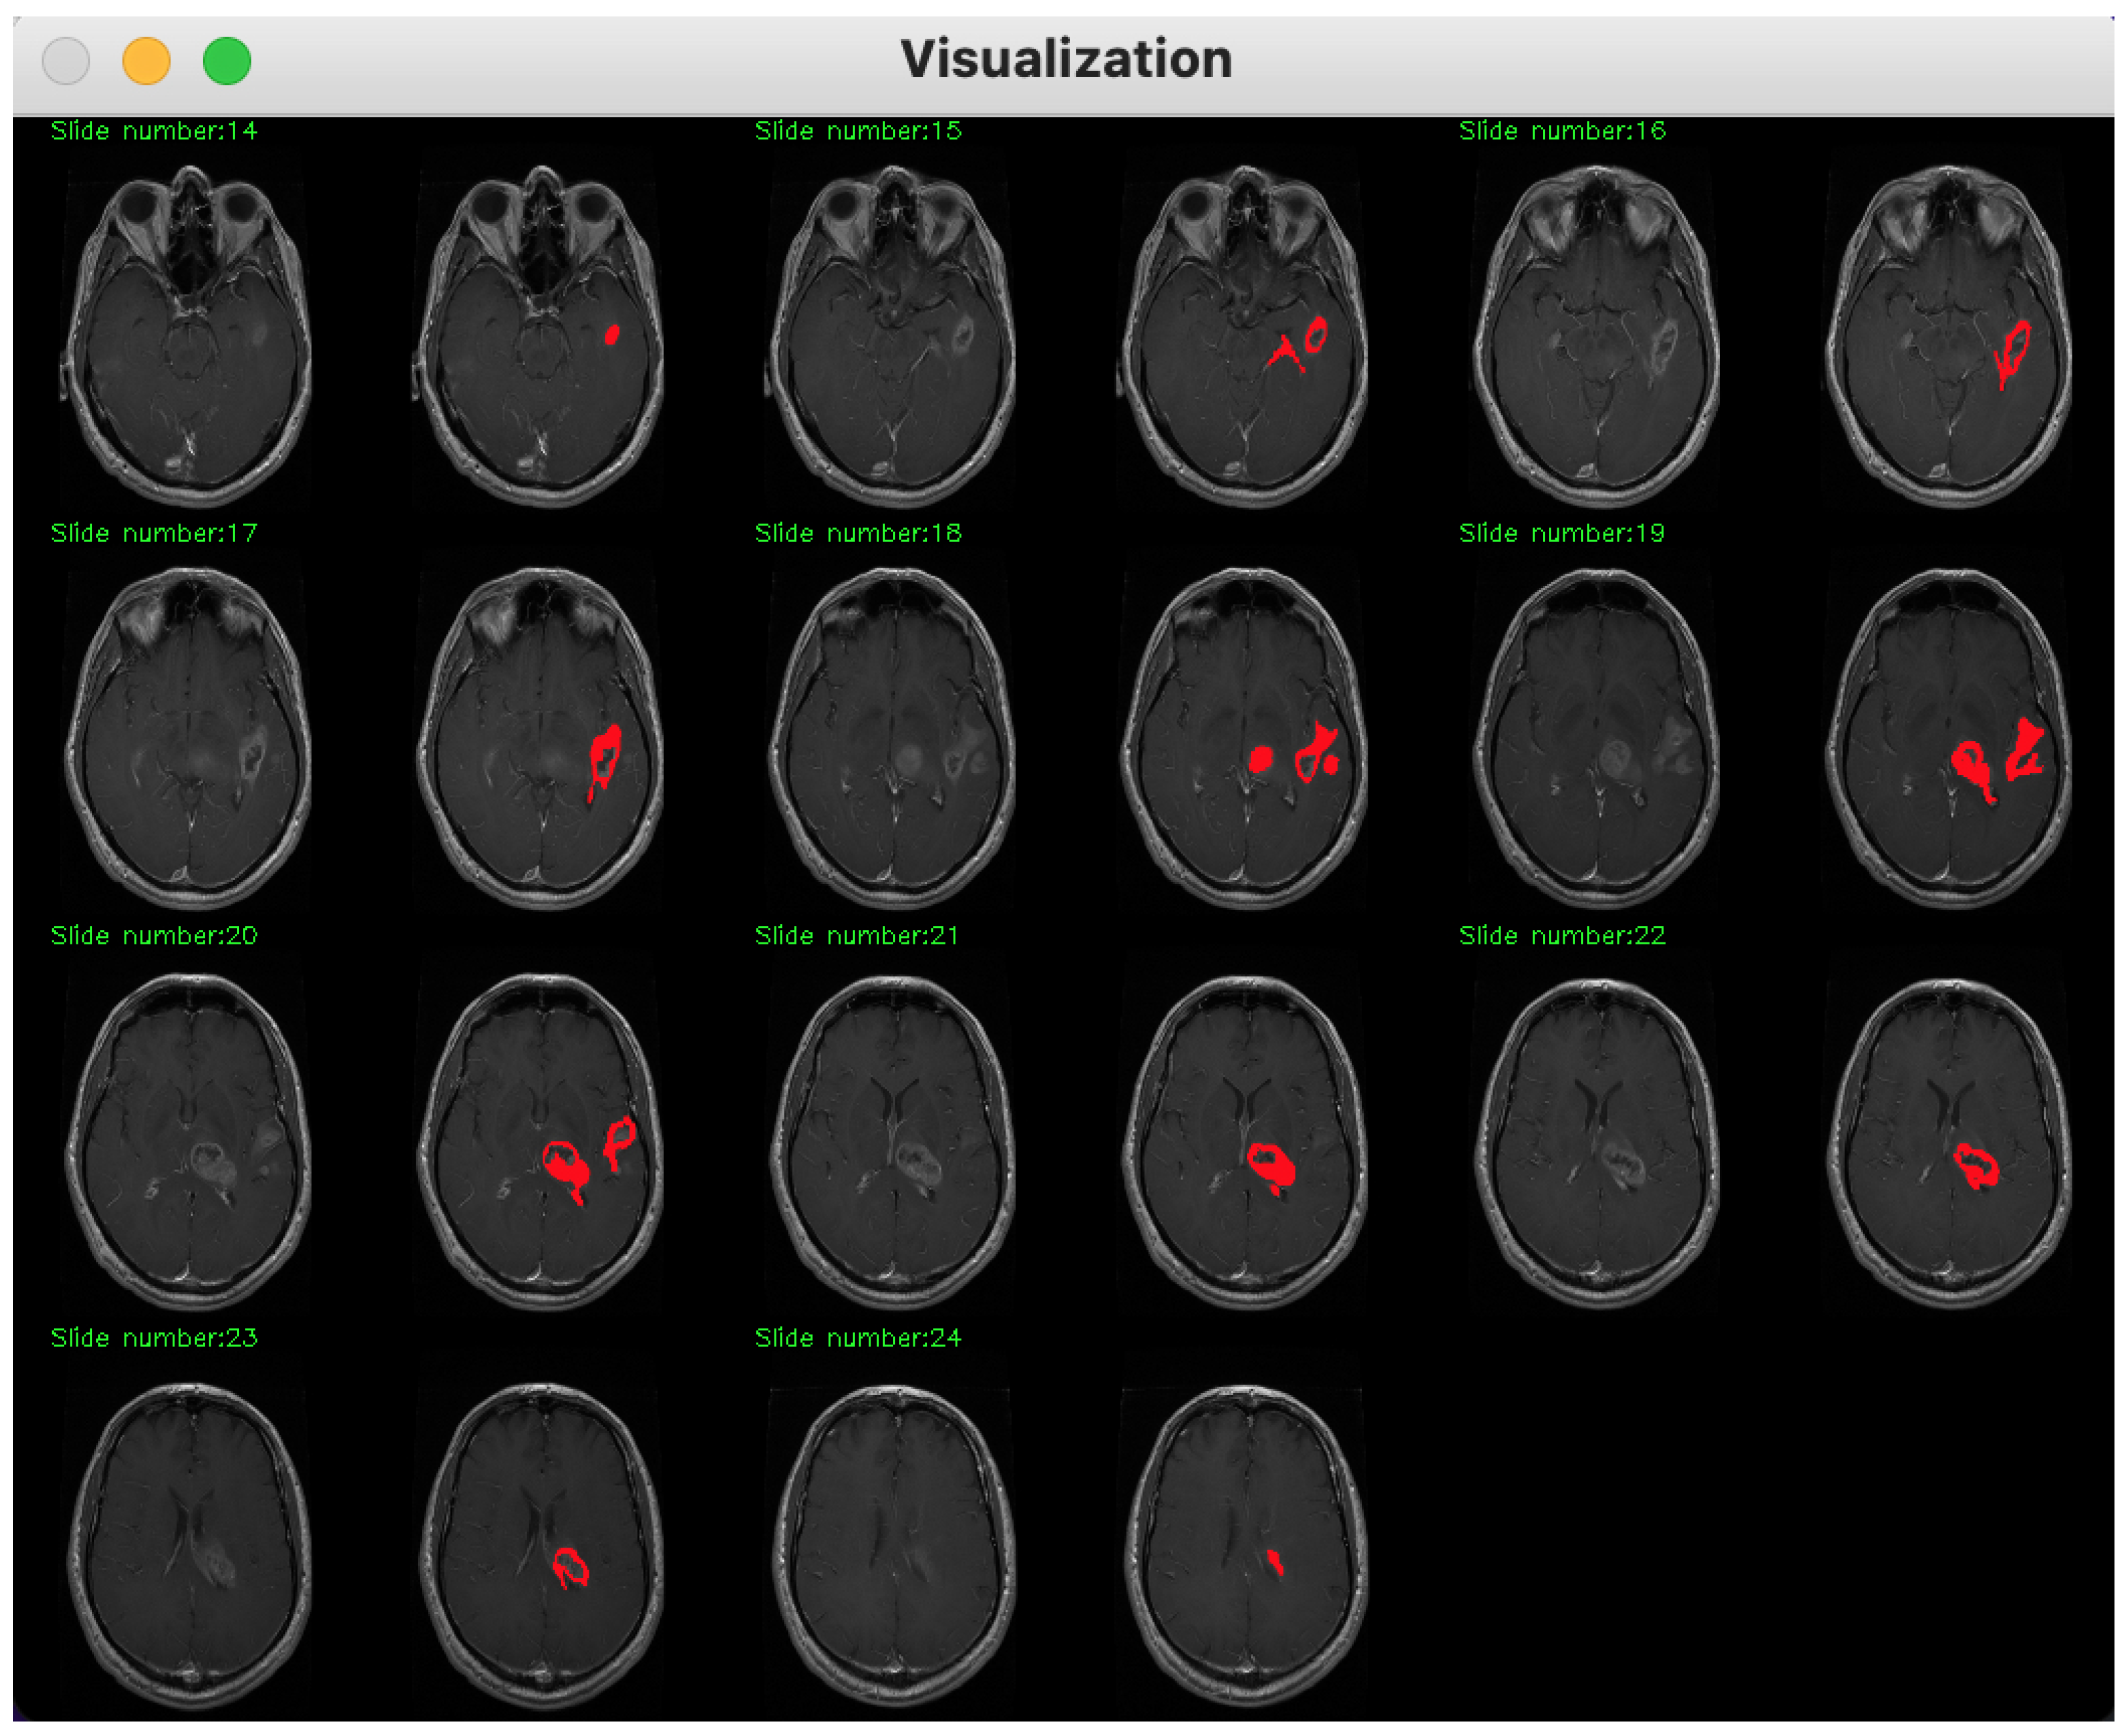

2. Method Description

3. Database Description

4. Experimental Assessment